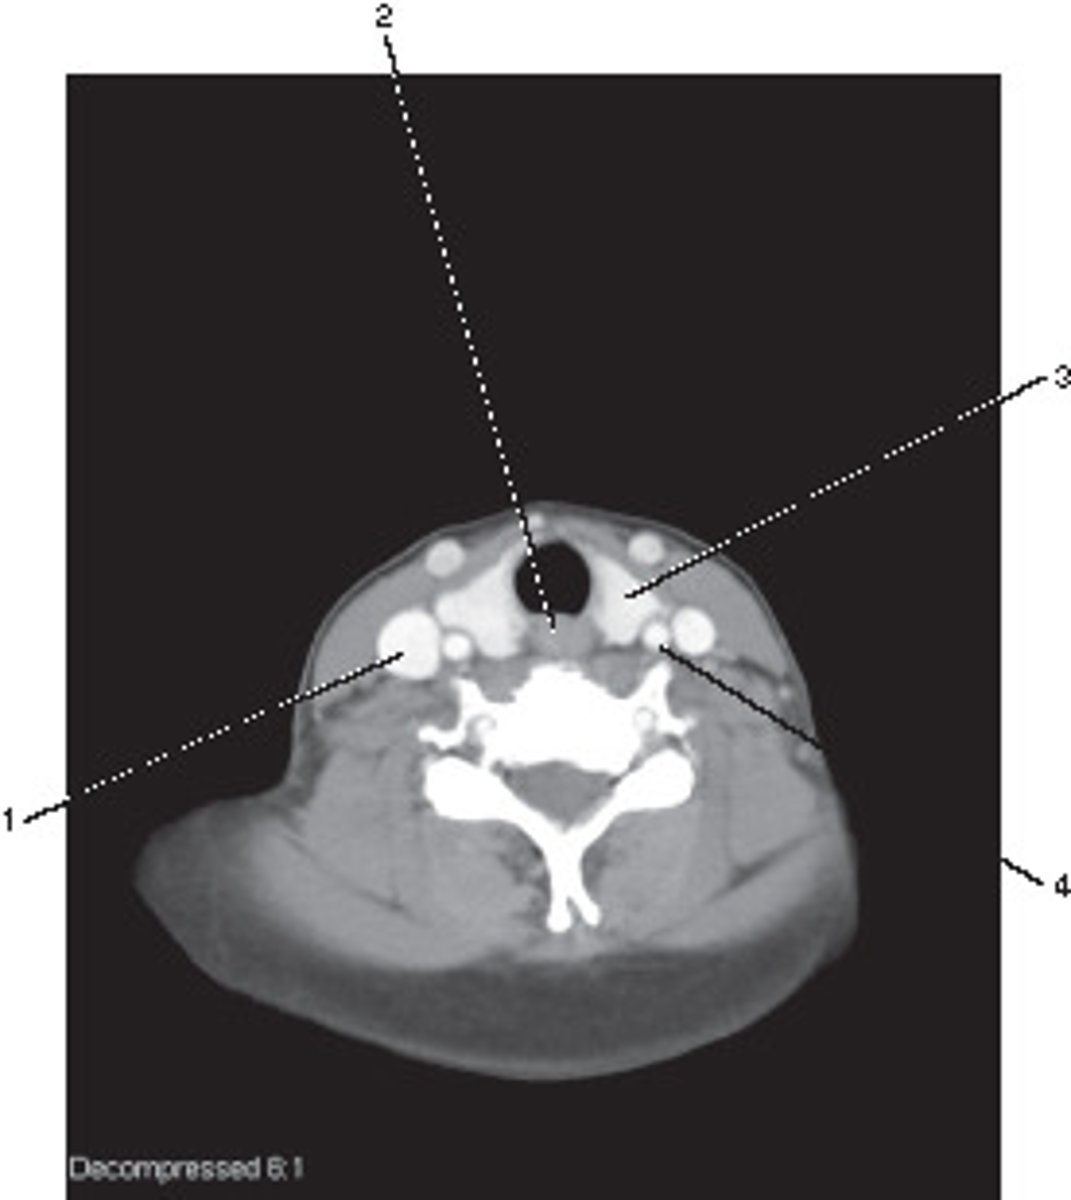

Left Common Carotid Artery

Number 4 corresponds to which of the following?

<p>Number 4 corresponds to which of the following?</p>

Common Carotid Artery

Number 5 corresponds to which of the following?

<p>Number 5 corresponds to which of the following?</p>

Vertebral Artery

Number 3 corresponds to which of the following?

<p>Number 3 corresponds to which of the following?</p>

Enlarged Thyroid

What pathological process best describes the abnormal finding in this image?

<p>What pathological process best describes the abnormal finding in this image?</p>

Thyroid Gland

Number 1 corresponds to which of the following?

<p>Number 1 corresponds to which of the following?</p>